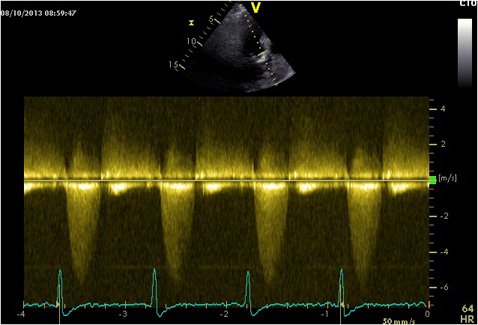

Apical 5 chamber view, apical five chamber view, view for determining the LVOT VTI and Vmax, Vmin, Vaverage ... View Video

Cardiac output (CO, r is the valve radius, and, VTI is the velocity time integral of the trace of the Doppler flow profile. but the exact steps needed to achieve clinically adequate precision have never been disclosed. 2D measurement of the aortic valve diameter is one source of noise; ... Read Article

Echocardiographic Assessment of Valve Stenosis: EAE/ASE Recommendations for Clinical Practice VTI AV Figure 3 An example of moderate aortic stenosis (left) and dynamic outflow obstruction in hypertrophic cardiomyopathy (right). ... Read Document